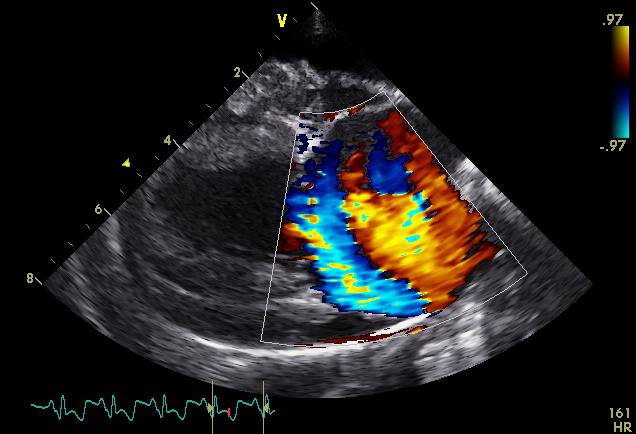

Bij cardiologische patiënten worden auscultatie, elektrocardiografie, Holter-monitoring (24u ECG) en echocardiografie met Doppler door ons uitgevoerd. Daarnaast wordt ook onderzoek verricht naar oorzaak, diagnose en therapie van congenitale en verworven hartaandoeningen bij honden, katten en andere diersoorten.